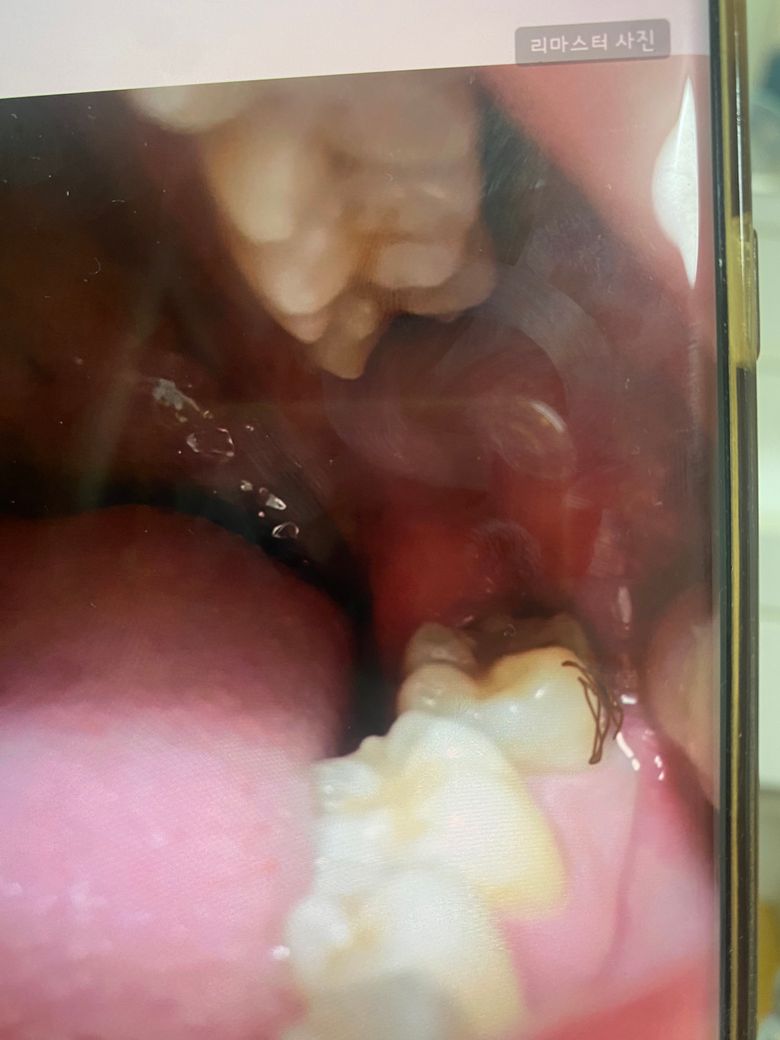

어금니 쪽 옆면 충치인가요? 치석인가요?

갈색으로 표시된 곳 에 갈색으로 되어있더라구요

저기로 찬거 먹으면 시리긴했는데 씹는면엔

검은색 작은 실처럼 충치가있는데

인접면은 오늘 처음봤는데 잇몸쪽에

갈색으로 되어있더라구요...

그것도 충치일까요... 레진으로 치료할 수 있는건가요?

아니면 크라운 씌워야하나요...

갈색으로 변색된 치아와 검은색 실 같은 충치가 보이는 경우 충치일 가능성이 높습니다.

충치가 깊지않고, 비교적 초기 단계이거나 크지 않다면, 레진으로 충분히 치료할 수 있습니다. 하지만 충치가 심하게 진행되어 치아가 손상된 경우에는 크라운치료가 필요됩니다.